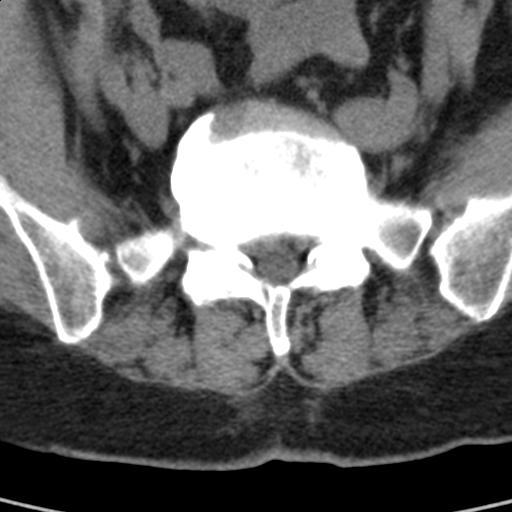

患者;女性;左下肢疼痛。

l5s1显示椎间盘突出,椎体边缘骨质增生,双侧黄韧带钙化。(请上传骨窗)

l5s1显示椎间盘突出,椎体边缘骨质增生,双侧黄韧带钙化 ,两侧椎小关节肥大,关节面硬化,关节间隙变窄,提示:椎小关节综合症

双侧的侧隐窝有狭窄。

我认为应该考虑为:l5s1椎间盘膨出,余(椎小关节退变、黄韧带钙化、椎间孔狭窄)与各位同行无异议。

l5s1显示椎间盘膨出,突出,椎体边缘骨质增生向后压迫硬膜囊,双侧黄韧带钙化,小关节面综合征

l5s1椎间盘向后脱出使脊膜囊受压,椎体边缘骨质增生,双侧黄韧带钙化。l45椎间盘估计亦突出,为何未扫。